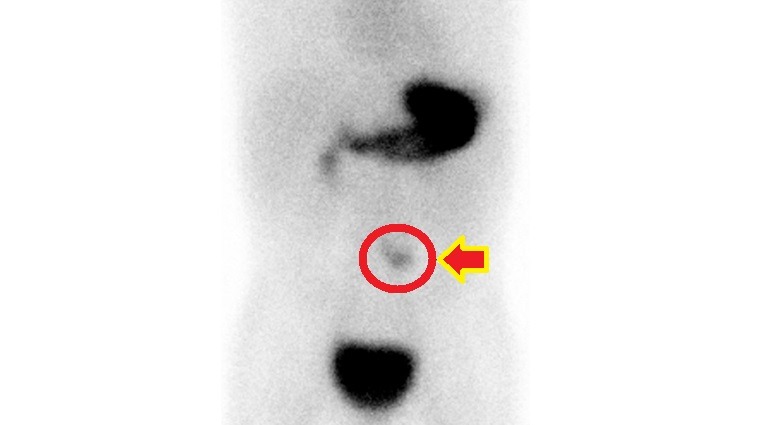

梅克爾憩室診斷主要靠梅克爾核醫掃描檢查,顯示異位性胃黏膜組織,若出現臨床症狀,以手術切除為主要治療方式。梅克爾憩室或其併發症因早期症狀不典型,臨床上易與腸胃炎混淆。徐千婷醫師呼籲,若孩子出現大片血便,或嚴重腹痛等異狀,應盡早就醫檢查,及時治療。